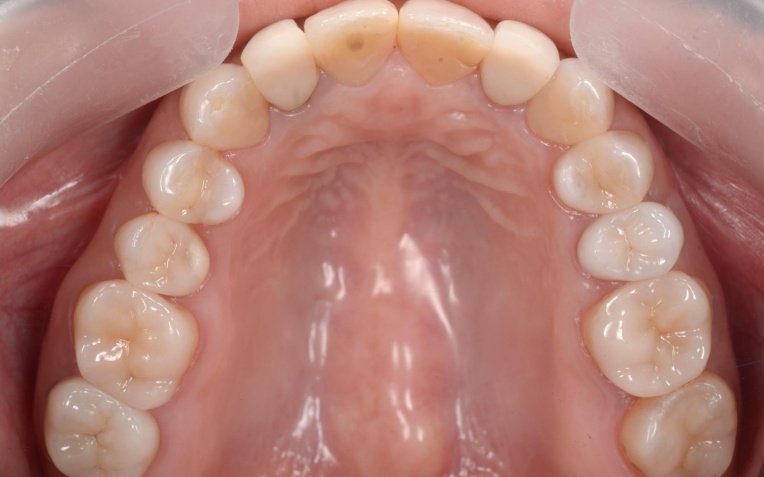

「そろそろ全体的に歯の治療をしたい」とご来院いただきました。 |

拝見したところ、左右下の奥歯が数本抜けたままになっており隙間が空いていました。 |

残っている歯を長く健康に保つためには、歯並びを整えて口腔内環境を根本から改善する治療が望ましいため、以下の総合的な治療計画を提案し同意いただきました。 |